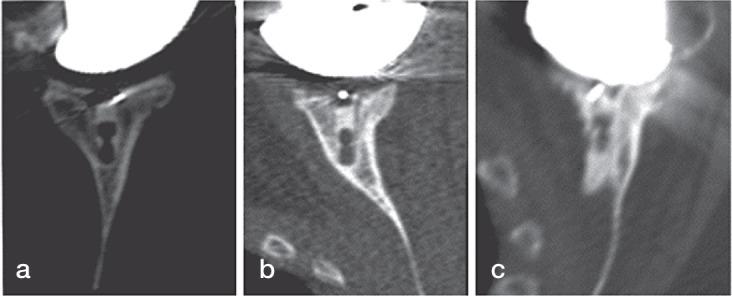

We used preoperative and postoperative CT scans of 29 TSAs to assess version, inclination, rotation, and offset of the glenoid relative to the scapula plane. The position of the implant keel within the glenoid vault was classified into three types: centrally positioned, component touching vault cortex, and perforation of the cortex.

Preoperative glenoid erosion was statistically significantly linked to the postoperative placement of the implant regarding all position parameters. Retroversion of the eroded glenoid was on average 10° (SD10) and retroversion of the implant after surgery was 7° (SD11). The implant keel was centered within the vault in 7 of 29 patients and the glenoid vault was perforated in 5 patients. Anterior cortex perforation was most frequent and was associated with severe preoperative posterior erosion, causing implant retroversion.